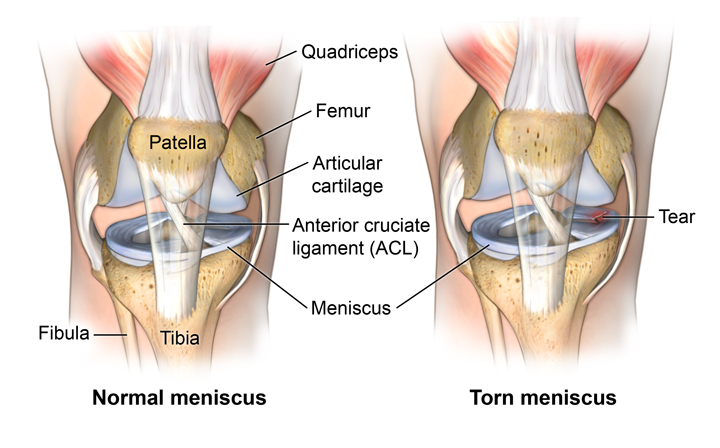

Know More About Meniscal Injuries

What are Meniscal Injuries/ Tears?

The femur (thigh bone) and tibia (shin bone) are separated by a soft tissue called the meniscus, which serves as a stress absorber. The medial (knee’s inner aspect) and lateral (knee’s outer aspect) menisci are two separate menisci in each knee.

One of the most frequent conditions that orthopaedic surgeons treat nowadays is meniscal tears. Meniscus damage should be corrected as soon as possible since it affects knee mobility and how forces are distributed within the knee joint.

What are the causes or symptoms?

- Acute meniscus tears result from a sudden twisting or pivoting manoeuvre.

- Acute meniscus tears are sometimes associated with ACL injuries.

- Meniscus tears, cause immediate pain over the specific meniscus.

- Potentially swelling and bruising. Loss of motion and strength.

- Clicking or catching while walking and increased pain while twisting on the affected foot.

- The knee may feel locked (aka – bucket handle meniscus).